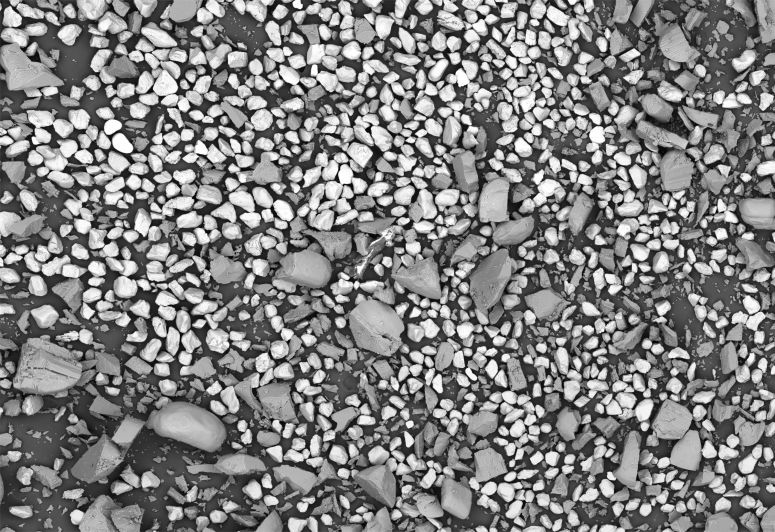

扫描电镜的探测器通常有两种:背散射电子(BSE)探测器和二次电子(SE)探测器。背散射电镜探测器在药物颗粒研究中最主要的优势在于:可以很好的展现材料的成分衬度像,即原子序数不同的粒子在 BSE 图像中显示出不同的亮度。这样,就可以很容易地从混合物(如辅料混合物)中区别出单个或主体颗粒的特性。

对飞纳台式扫描电镜进行编程,可以自动拍摄扫描电镜(SEM)图像并获得拼图,还可以使用颗粒统计分析测量系统(Particlemetric)对识别到的颗粒进行测量和统计分析。下图拍摄视野为 5.3 x 3.6 mm,分辨率为 500 nm。

通过灰度可以区别出不同材料并得到关键特征信息。如上图所示,较深灰色颗粒具有宽尺寸分布范围,平均当量圆直径为 35±31 µm。较浅灰色颗粒尺寸分布范围较窄,平均当量圆直径为 80±31 µm。在这个过程中,系统识别并测量了 3000 多个颗粒,且完成自动拼图和颗粒统计分析的总时间不到 20 分钟。